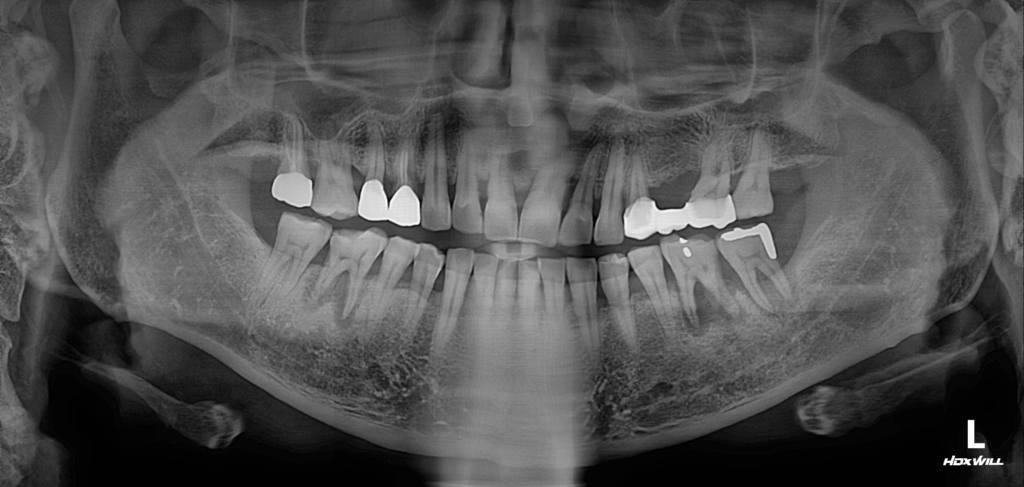

술전 사진

25.01

이 환자분은 양쪽 하악에 불편함을 호소하며 내원하셨습니다.

사진에서 보이는 우측(좌측 하악)의 경우, 6번과 7번 치아에 심각한 치주염이 있었고,사진의 좌측(우측 하악)에서는 6번 치아에만 치주염이 깊게 진행된 상황이었습니다.

치주염이 심각했기 때문에 지속적인 통증이 있었고, 이로 인해 골소실도 상당히 진행되었습니다.따라서 해당 부위에 GBR(유도골재생술)을 적용하여 골이식을 진행하고, 그 후 임플란트를 식립하는 치료 계획을 세웠습니다.